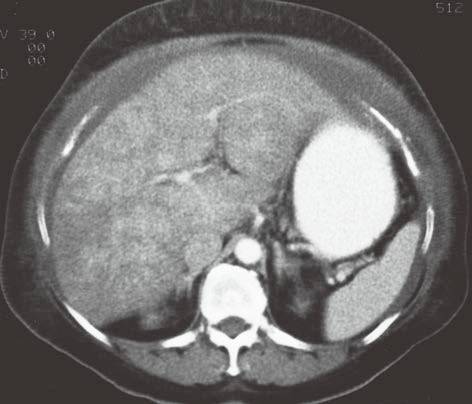

| 脂肪浸润(图1〜图 3) | 肝脏密度弥漫性减低。在肝脏脂肪变的低密度背景下,门静脉表现为高密度结构(平扫时正常门静脉呈低密度)。 | 由于三酰甘油过度沉积所致,见于肝硬化或其他肝脏疾病。正常肝脏平均CT值不低于脾脏,肝脏脂肪 浸润时CT密度较低。肝硬化引起脂肪浸润,伴有肝右叶萎缩,尾状叶体积增大。 |

图2肝硬化患者的肝内斑片状脂肪浸润